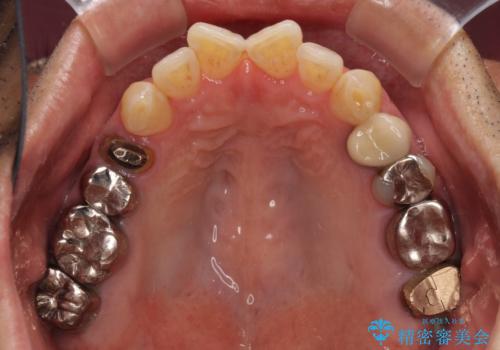

- 奥歯に違和感を感じており、抜歯の必要性を感じて来院された患者様です。

診査の結果、5本の奥歯を抜歯してインプラントによる補綴治療が必要と診断されました。

患者様が違和感を感じていない左下の奥歯の治療は今回は見送り、それ以外の治療が必要な奥歯を治療することとしました。